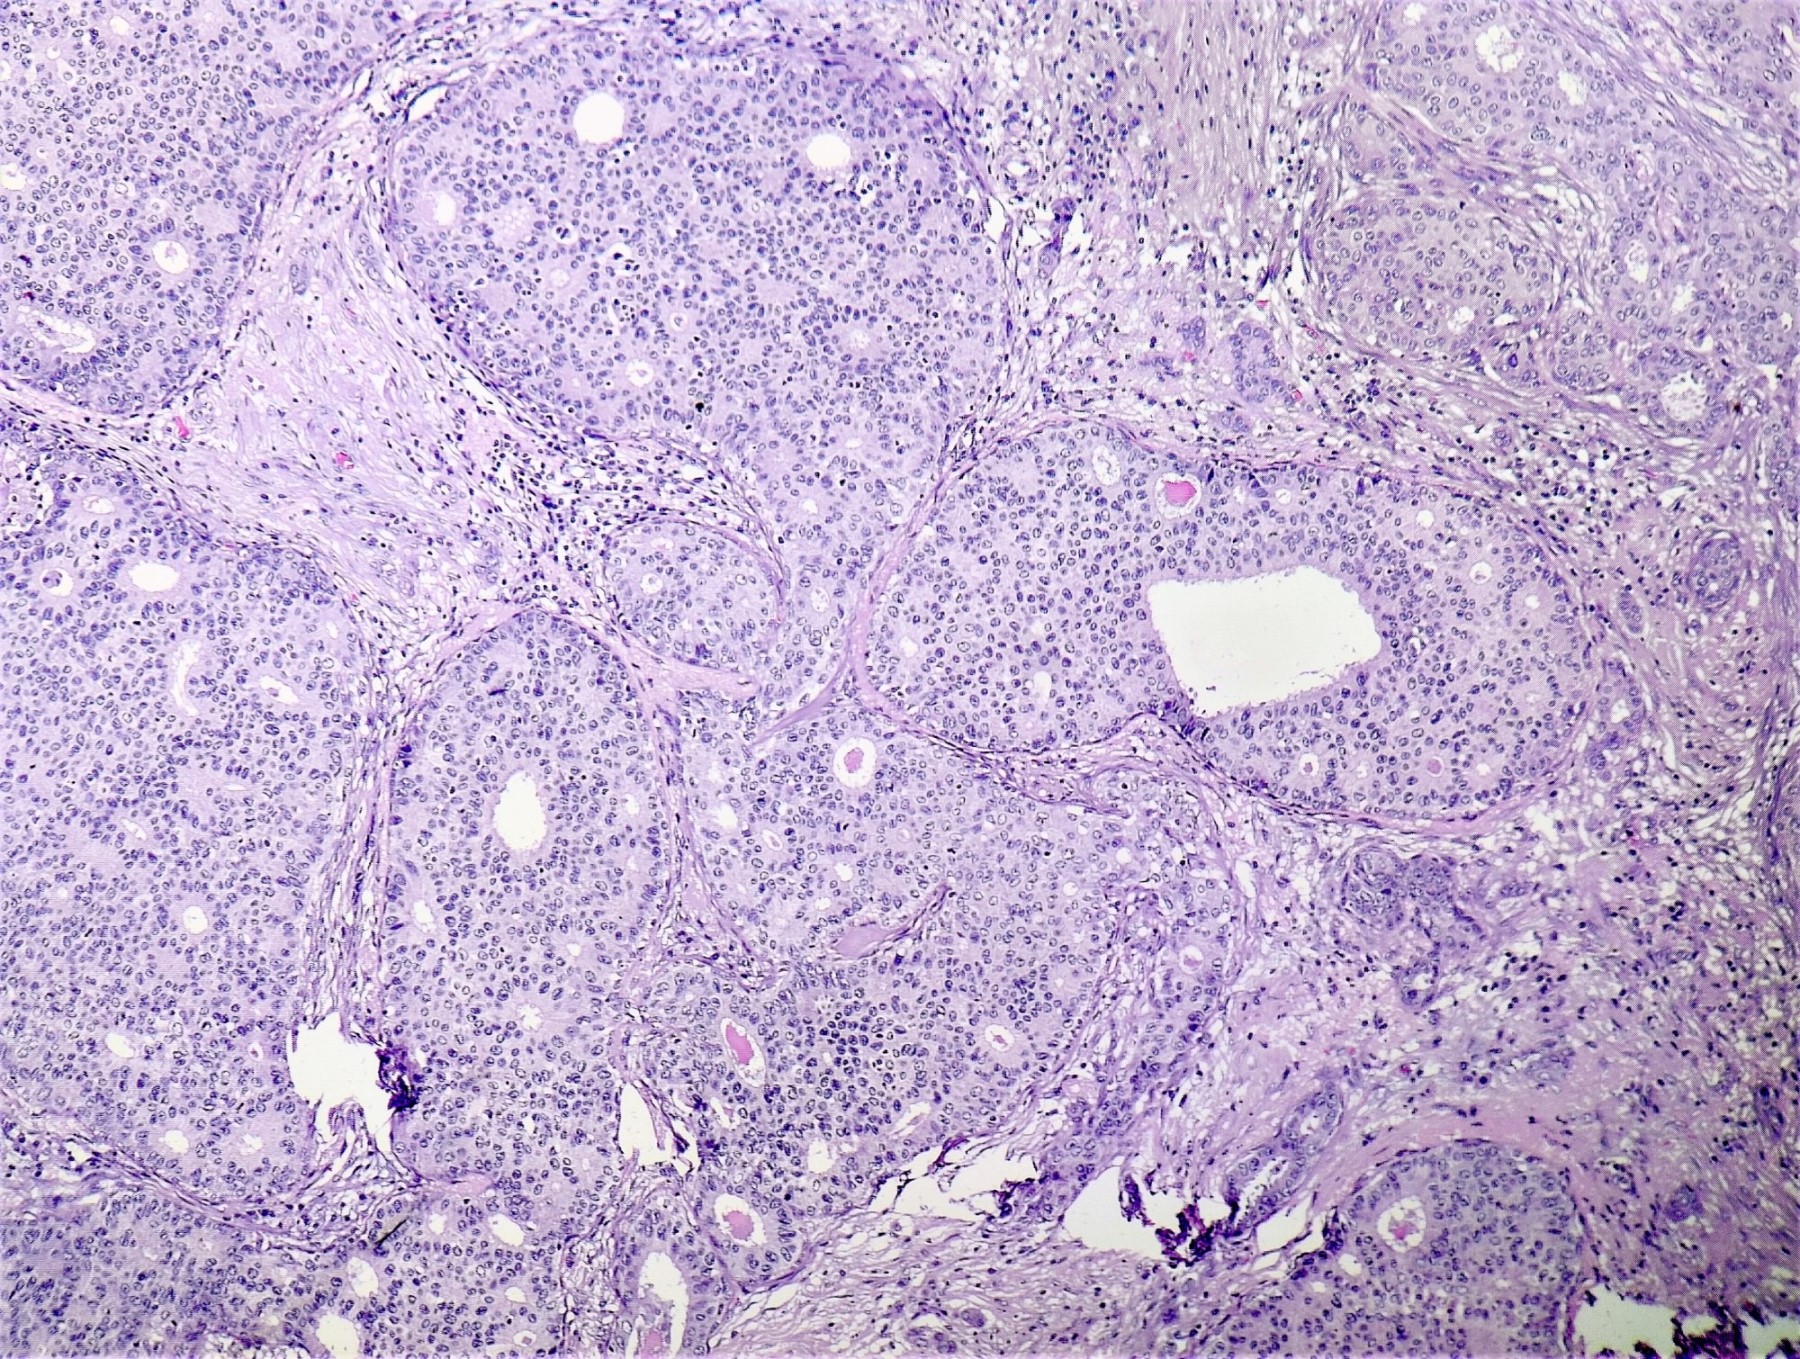

Microscopic (histologic) description

- Irregular cribriform growth pattern > 90% of cells

- Nuclear grade I pure ICC: > 90% cribriform pattern

- Mixed: 10 - 90% other morphological type, other than cribriform carcinoma

- Low grade: Nottingham grade 1 tumors

- Invasive islands or nests of malignant cells with round or angulated contours and well defined cribriform spaces formed by arches of epithelial cells; this gives a sieve-like appearance

- Tumor cells: small, mild / moderate pleomorphism, no nuclear atypia

- No / sparse mitotic activity

- Desmoplastic stroma

- Mucin positive secretion, microcalcifications in lumen

- Osteoclastic giant cells may be seen

- Myoepithelial cells absent

- Associated with cribriform ductal carcinoma in situ (DCIS)

Microscopic (histologic) images

Contributed by Sunitha Shankaralingappa, M.B.B.S, M.D., D.M.